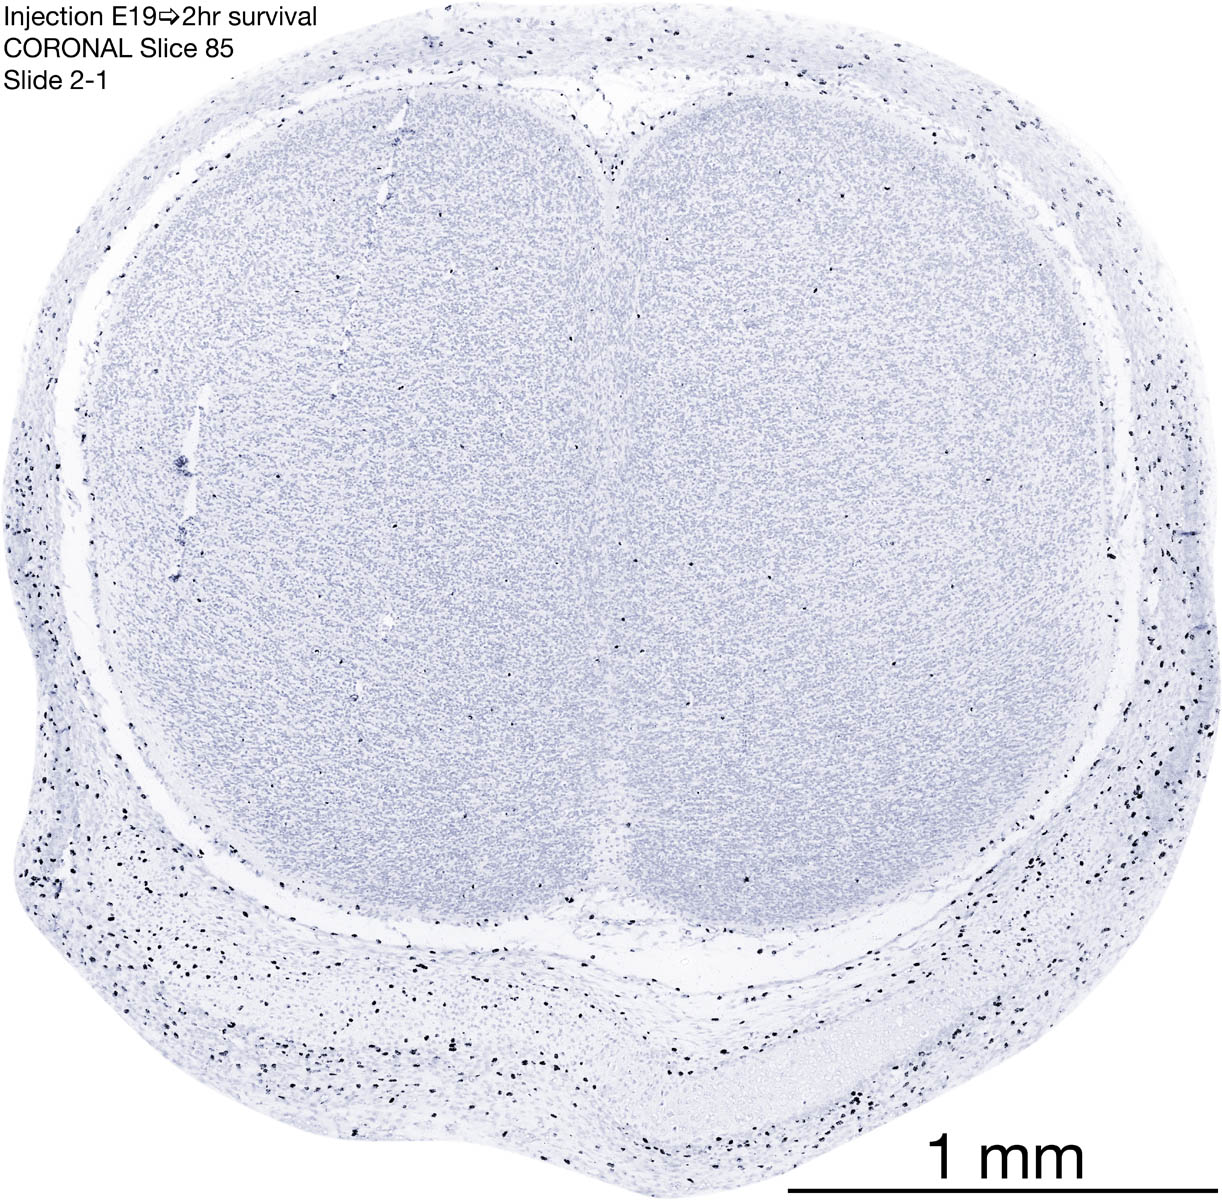

E19 2hr Survival Archived Images-Coronal The following images are from a paraffin-embedded coronally-sectioned head of an E19 rat embryo exposed to tritiated thymidine 2 hours before death. Download: Large | High Res Download: Large | High Res Download: Large | High Res Download: Large | High Res Download: Large | High Res Download: Large | High Res Download: Large | High Res Download: Large | High Res Download: Large | High Res Download: Large | High Res Download: Large | High Res Download: Large | High Res Download: Large | High Res Download: Large | High Res Download: Large | High Res Download: Large | High Res Download: Large | High Res Download: Large | High Res Download: Large | High Res Download: Large | High Res Download: Large | High Res Download: Large | High Res Download: Large | High Res Download: Large | High Res Download: Large | High Res Download: Large | High Res Download: Large | High Res Download: Large | High Res Download: Large | High Res Download: Large | High Res Download: Large | High Res Download: Large | High Res Download: Large | High Res Download: Large | High Res Download: Large | High Res Download: Large | High Res Download: Large | High Res Download: Large | High Res Download: Large | High Res Download: Large | High Res Download: Large | High Res Download: Large | High Res Download: Large | High Res Download: Large | High Res Download: Large | High Res Download: Large | High Res Download: Large | High Res Download: Large | High Res Download: Large | High Res Download: Large | High Res Download: Large | High Res Download: Large | High Res Download: Large | High Res Download: Large | High Res Download: Large | High Res Download: Large | High Res Download: Large | High Res Download: Large | High Res Download: Large | High Res Download: Large | High Res Download: Large | High Res Download: Large | High Res Download: Large | High Res Download: Large | High Res Download: Large | High Res Download: Large | High Res Download: Large | High Res Download: Large | High Res Download: Large | High Res Download: Large | High Res Download: Large | High Res Download: Large | High Res Download: Large | High Res Download: Large | High Res Download: Large | High Res Download: Large | High Res Download: Large | High Res Download: Large | High Res Download: Large | High Res Download: Large | High Res Download: Large | High Res Download: Large | High Res Download: Large | High Res Download: Large | High Res Download: Large | High Res Download: Large | High Res Download: Large | High Res Download: Large | High Res Download: Large | High Res Download: Large | High Res